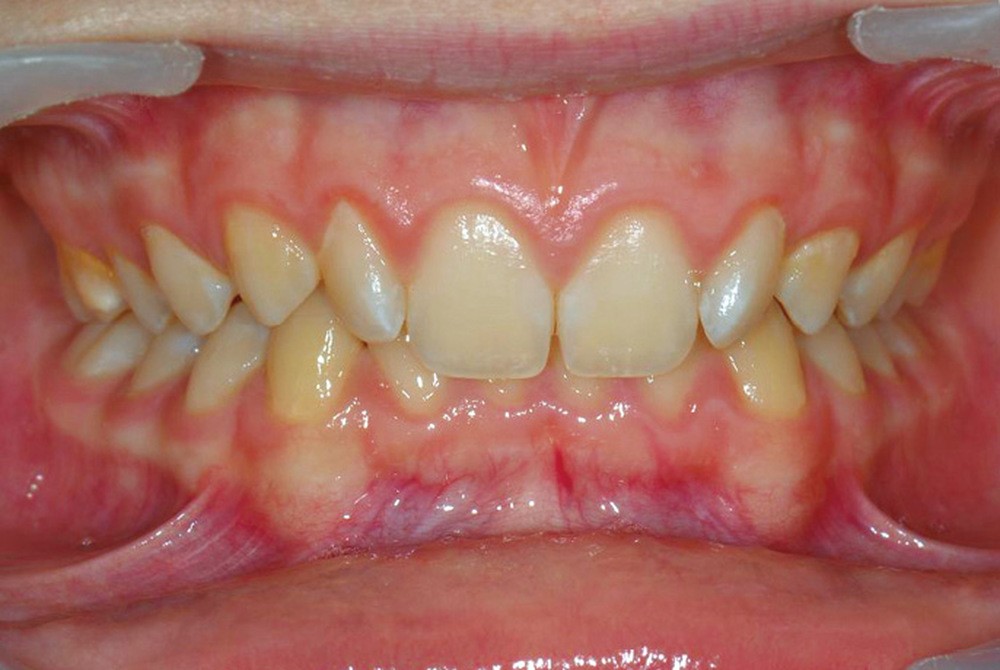

Son profil convexe s’inscrit dans un contexte de classe II squelettique par rétrognathie mandibulaire normodivergente sur un schéma de Classe II/2 avec supraclusion et encombrement modéré (fig. 1 à 7).

La formule dentaire est complète, avec un léger retard d’évolution des deuxièmes molaires (fig. 8).

Le parodonte est de type 1 selon la classification de Maynard et Wilson.